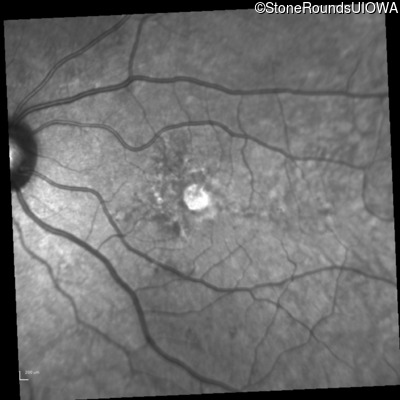

Infrared Fundus Photograph - Right - 20/20 +2

Exemplar

Infrared Fundus Photograph - Left - 20/40 -2